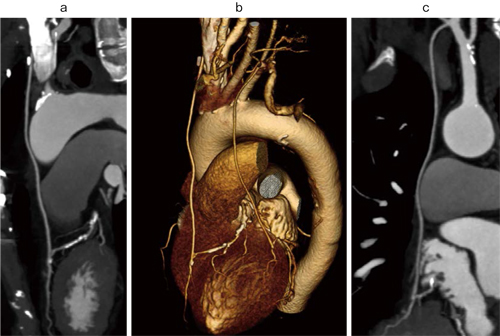

2012年春に発売を開始した最新型64スライスCT「SOMATOM Perspective」でも使用可能であり,さまざまな検査に適応されている(図1)。

図1 2012年春に発売を開始した最新型64スライスCT

「SOMATOM Perspective」による心臓CT画像

a:Curved MPR b:Volume Rendering c:Curved MPR

バイパス後フォローアップ症例。SAFIREを使用し,被ばく低減を推進。